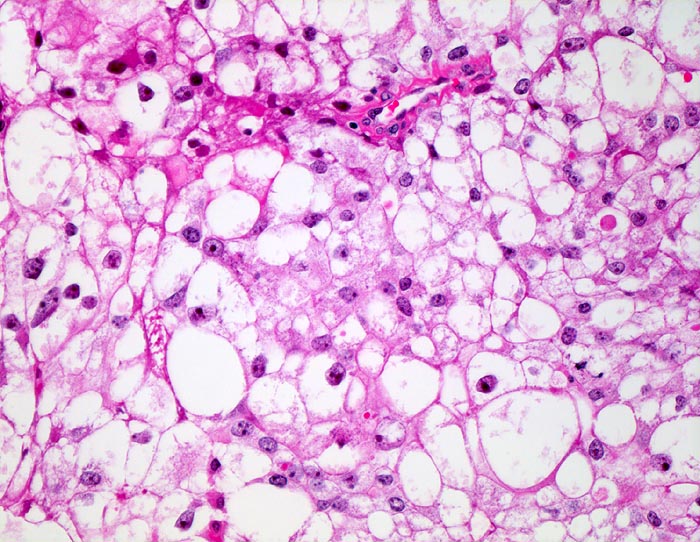

Tumorzellen mit deutlichen Zellgrenzen. Das reichlich vorhandene Zytoplasma ist entweder klar oder fein granulär eosinophil. Die Zellkerne sind polymorph, deutlich grösser als Zellkerne eines Nierentubulus und enthalten schon bei schwacher Vergrösserung gut erkennbare Nukleolen entsprechend einem mässig differenzierten Karzinom.

Beim hellzelligen Nierenzellkarzinom erfolgt die Gradierung entsprechend der Kernmorphologie. Die meisten Karzinome fallen in die Kategorie der mässig differenzierten G2 Tumoren. Hoch differenzierte G1 Tumoren haben kleine runde Kerne mit feinen Nukleolen. Mitosen sind kaum nachweisbar. Bei wenig differenzierten G3 Karzinomen lassen sich neben stark vergrösserten hyperchromatischen Kernen mit stark vergrösserten Nukleolen auch mehrkernige Zellen nachweisen.